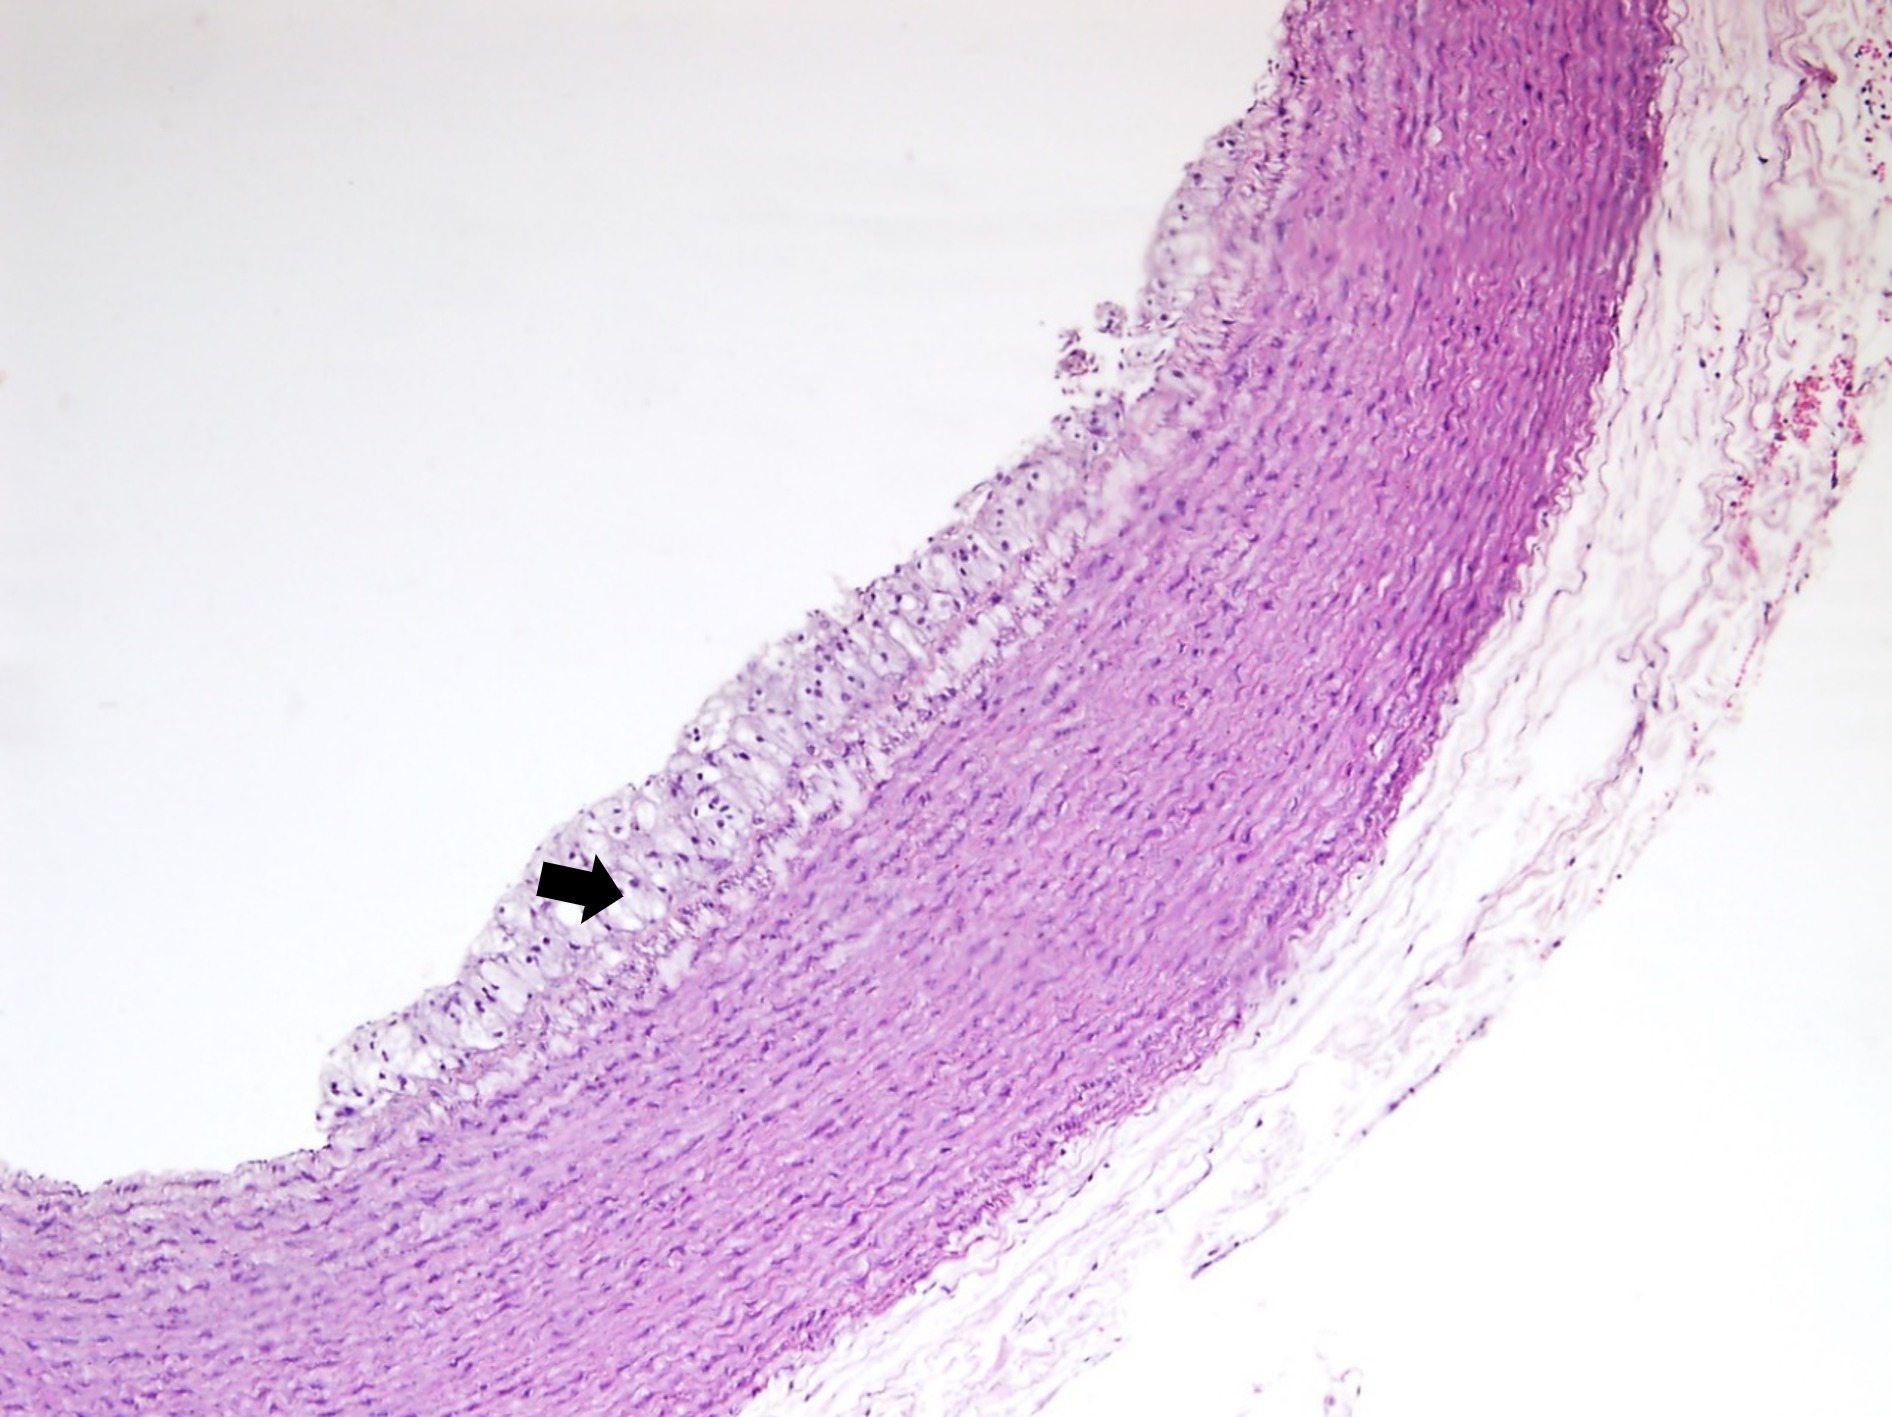

The histological examination of aorta in group A, the control group showed intact tunica intima with thin wavy corrugated endothelium, a normal subendothelial layer, and wavy internal elastic fibers. The tunica media is comprised of elastic fibers and smooth muscle. The outermost layer is the tunica adventitia and is made up of loose connective tissue (Figs. 7,8). In group B, the tunica intima showed the presence of focal thickening, filled with vacuolated cells or foam cells, resulting in the widening of the subendothelial layer (Fig. 9). The tunica intima of the aorta in group C showed intimal thickening with subendothelial collection of foam cells as well as formation of a lipid core and fibrous cap (Fig. 10).

Fig. 9.A photomicrograph of a section of aorta in group B stained by

hematoxylin and eosin (10